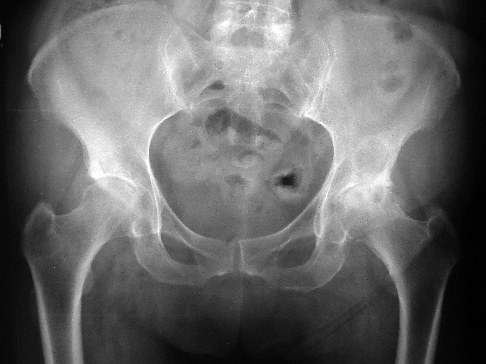

Wenn eine Hüftgelenksarthrose Ursache der Oberschenkelschmerzen ist, erkennt man dies am besten anhand eines Röntgenbildes. © NICOLAS LARENTO, Adobe

Bei Schmerzen im Oberschenkel klärt der Arzt strukturiert ab, ob Muskelverletzungen, Nervenreizungen oder Gefäßschäden die Ursache sind.

Bildgebung. In unklaren Fällen oder bei Hinweisen auf eine knöcherne Ursache zieht der Arzt meist das Röntgen heran. Darin sind Hüftgelenksarthrose, Knochenbrüche und Knochentumoren gut zu erkennen. Ist die Aufnahme auffällig, wird das konventionelle Röntgen oft durch eine CT ergänzt. Muskeln und Sehnen lassen sich gut durch Ultraschall darstellen. Für tiefere Strukturen oder Nerven zieht man eher eine MRT heran. Arteriosklerotische Gefäße untersucht man mithilfe der Duplex-Sonographie und, bei Bedarf, einer Angiographie.